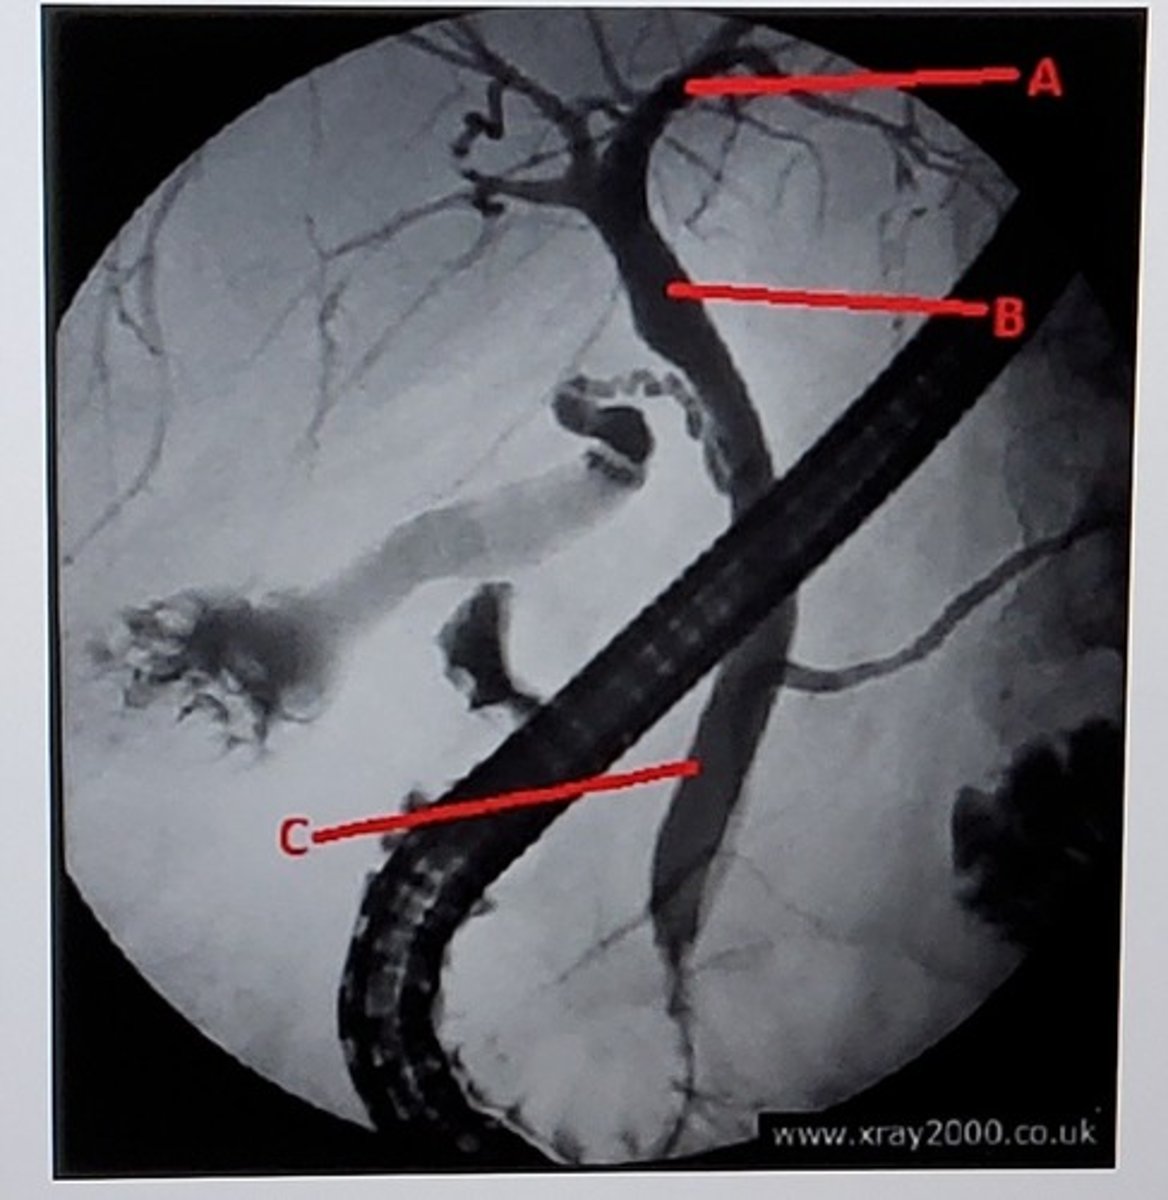

A. Duodenal bulb

B. Second/descending portion

C. Third/horizontal portion

D. Fourth/ascending portion

Identify the specific portions of the structure labeled with letters A, B, C, D.